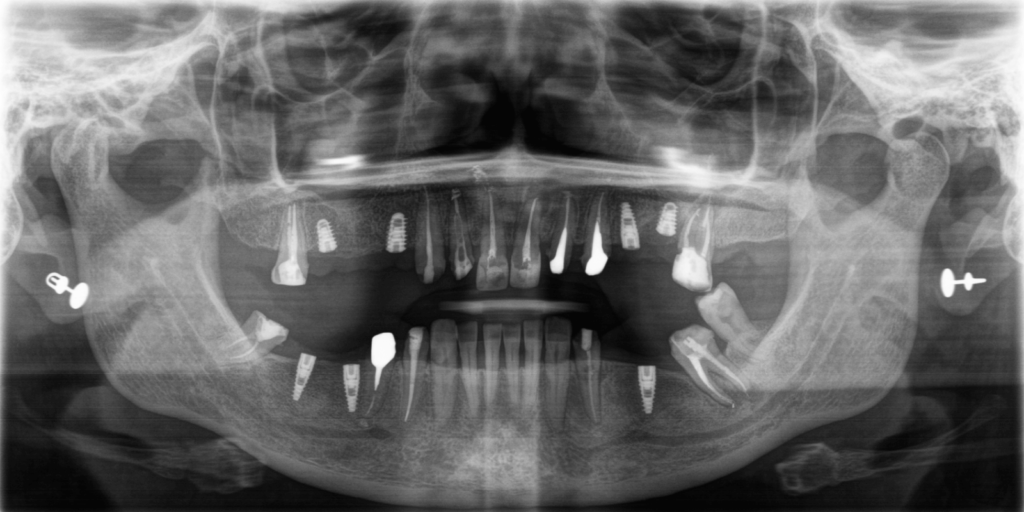

- Дополнительно, при изучении КТ, врач обнаружил гранулемы и кистогранулемы почти на всех опорных зубах под мостовидными конструкциями.

- Снять все ортопедические конструкции, провести тесты и выявить те зубы, которые мы можем сохранить.

- Провести эндолечение зубов, которые мы можем сохранить.

- Удалить зубы 2.5 и 3.8 в связи с высокой степенью подвижности и осложненным пародонтитом.

- Установить 4 зубных импланта на верхней челюсти и 3 на нижней.